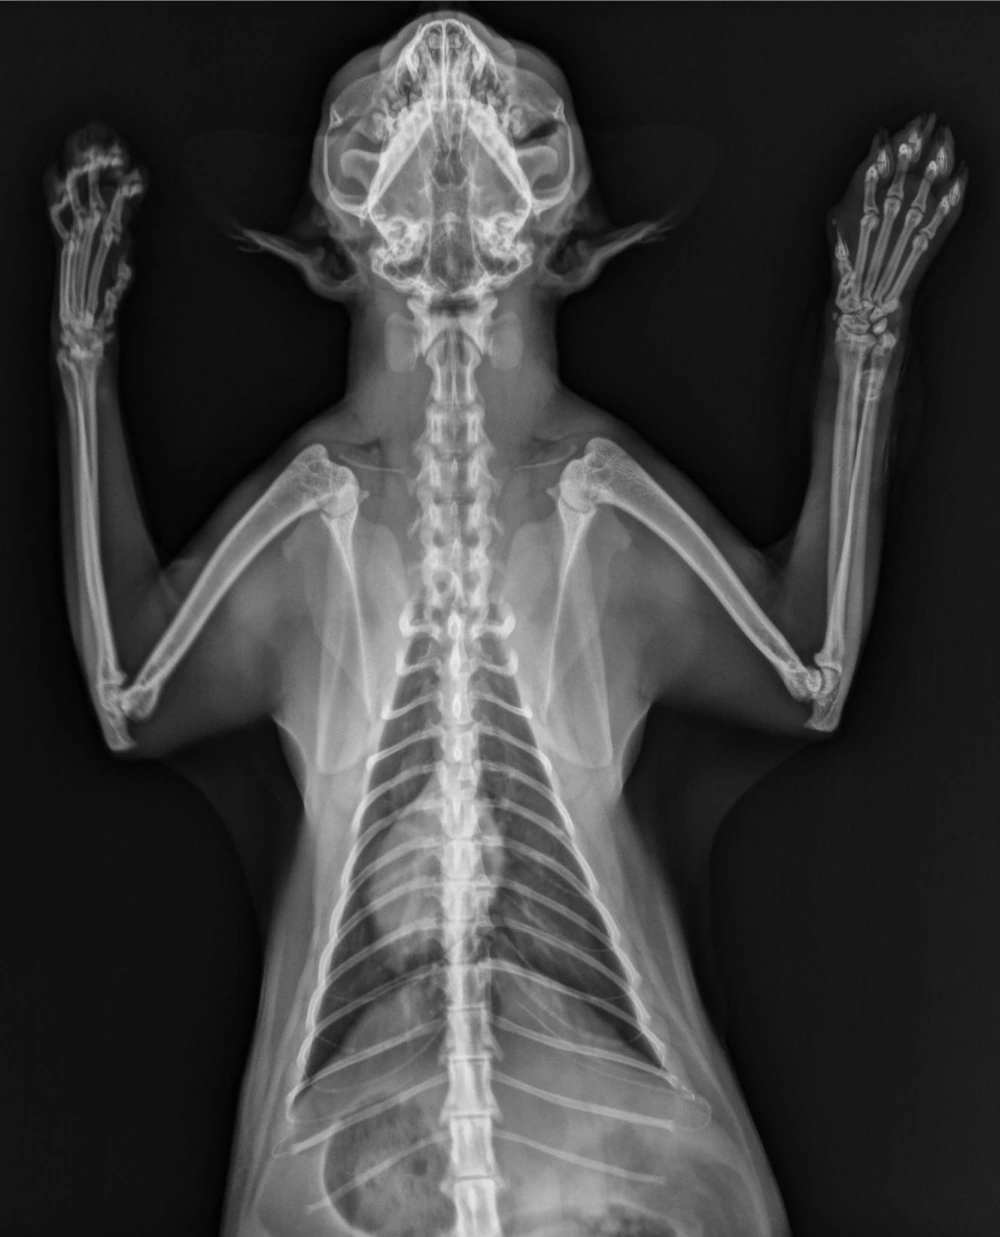

O raio x é uma das ferramentas mais importantes quando se trata da saúde dos animais de estimação.

Os exames de raio x são essenciais para identificar problemas ósseos, problemas respiratórios, obstruções internas, gestações e muitas outras condições que não são visíveis a olho nu.